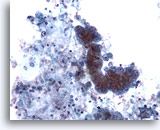

Un grupo de adenocarcinoma mezclado con macrófagos respiratorios.

20x